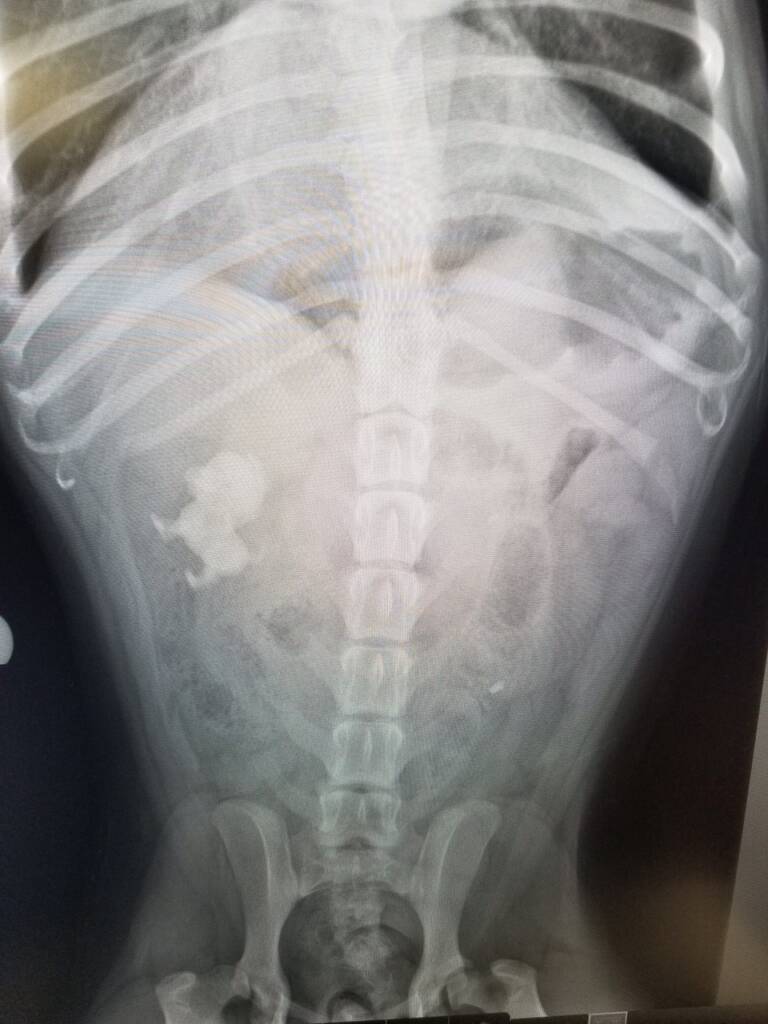

2021 They Ate What?! X-ray Contest winnersThey Ate This: Check out the winner, runners-up, and honorable mentions October 4, 2021 < Previous Entry VOTE NOW! Next Entry > Pages: 1 2 3 4 5 6 7 8 9 10 11 12 13 14